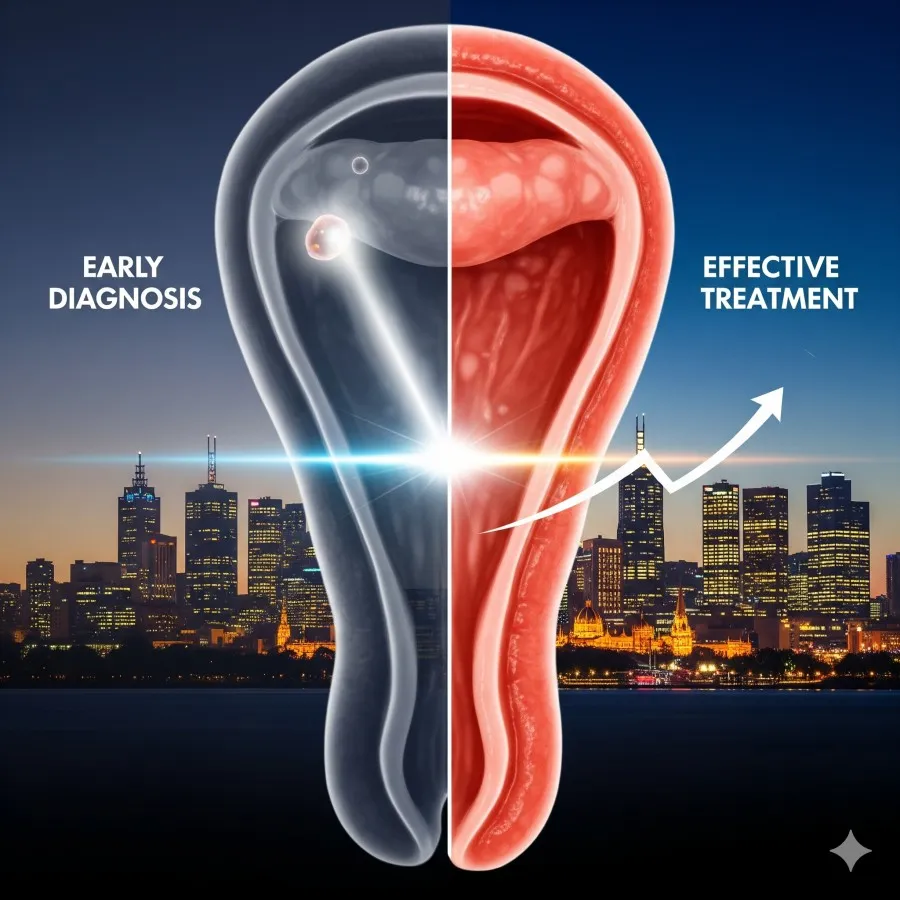

Welcome to Bayside Colorectal Group

Bayside Colorectal Group is a team of specialist colorectal surgeons, with Dr Paul Sitzler and Dr Vignesh Narasimhan. The group caters to the needs and geographic location of central and suburban Melbourne, with an emphasis on the bayside suburbs. The aim is to provide up-to-date quality service in the field of colorectal surgery. Through initial assessment, diagnosis, investigation, surgical treatment, and follow-up, the focus remains on efficient, state-of-the-art management.

Surgical Excellence. Better Personalized for You

At our surgical center, we combine advanced medical technology with compassionate, patient-centered care. Our team of highly trained surgeons brings years of expertise across a range of procedures, ensuring each patient receives precise

Common medical conditions that require evaluation